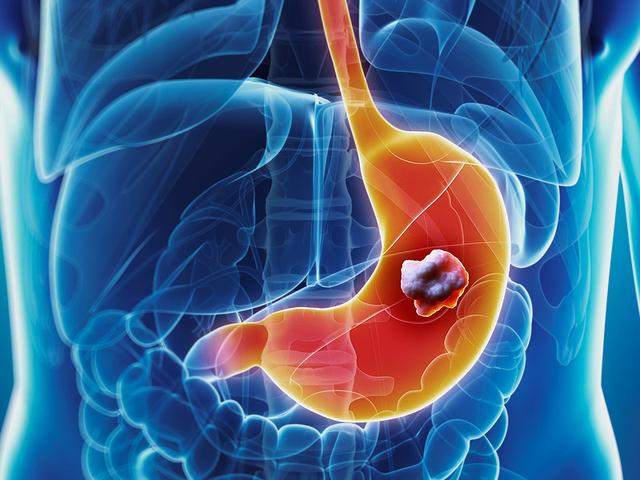

3. 胃癌:持續的胃灼熱

胃癌不是最常見的癌症,但它的發病率正在增加,患有胃食管反流病的人可能沒有意識到,他們的食道內膜正在發生變化,食道的正常健康細胞可能慢慢被癌細胞所取代。如果持續的胃灼熱與吞嚥困難或疼痛一起出現,更要當心。